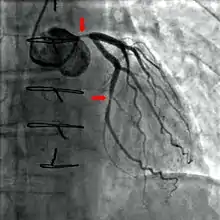

Coronary catheterization is one of the several cardiology diagnostic tests and procedures. Specifically, through the injection of a liquid radiocontrast agent and illumination with X-rays, [1] angiocardiography allows the recognition of occlusion, stenosis, restenosis, thrombosis or aneurysmal enlargement of the coronary artery lumens; heart chamber size; heart muscle contraction performance; and some aspects of heart valve function. Important internal heart and lung blood pressures, not measurable from outside the body, can be accurately measured during the test. The relevant problems that the test deals with most commonly occur as a result of advanced atherosclerosis – atheroma activity within the wall of the coronary arteries. Less frequently, valvular, heart muscle, or arrhythmia issues are the primary focus of the test.

If atheroma, or clots, are protruding into the lumen, producing narrowing, the narrowing may be seen instead as increased haziness within the X-ray shadow images of the blood/dye column within that portion of the artery; this is as compared to adjacent, presumed healthier, less stenotic areas.